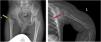

Skeletal sequelae were detected in 7 cases, of whom 6 had both SA and OM. Hip (3 cases) and shoulder (3 cases) were the main affected sites (Supplemental Material – Figure 1). Pathogen culture showed staphylococcus aureus infection in 5 cases (Table 2).

Sequelae of hip and shoulder in the follow-up. a, AP radiograph of the pelvis demonstrating severe deformity of the hip, including complete loss of femoral head and neck with no articulation of the hip, limb-length discrepancy and acetabular dysplasia (yellow arrow). b, Lateral-view radiograph of humerus showing the epiphysis of the proximal humerus are partially absent (red arrow).